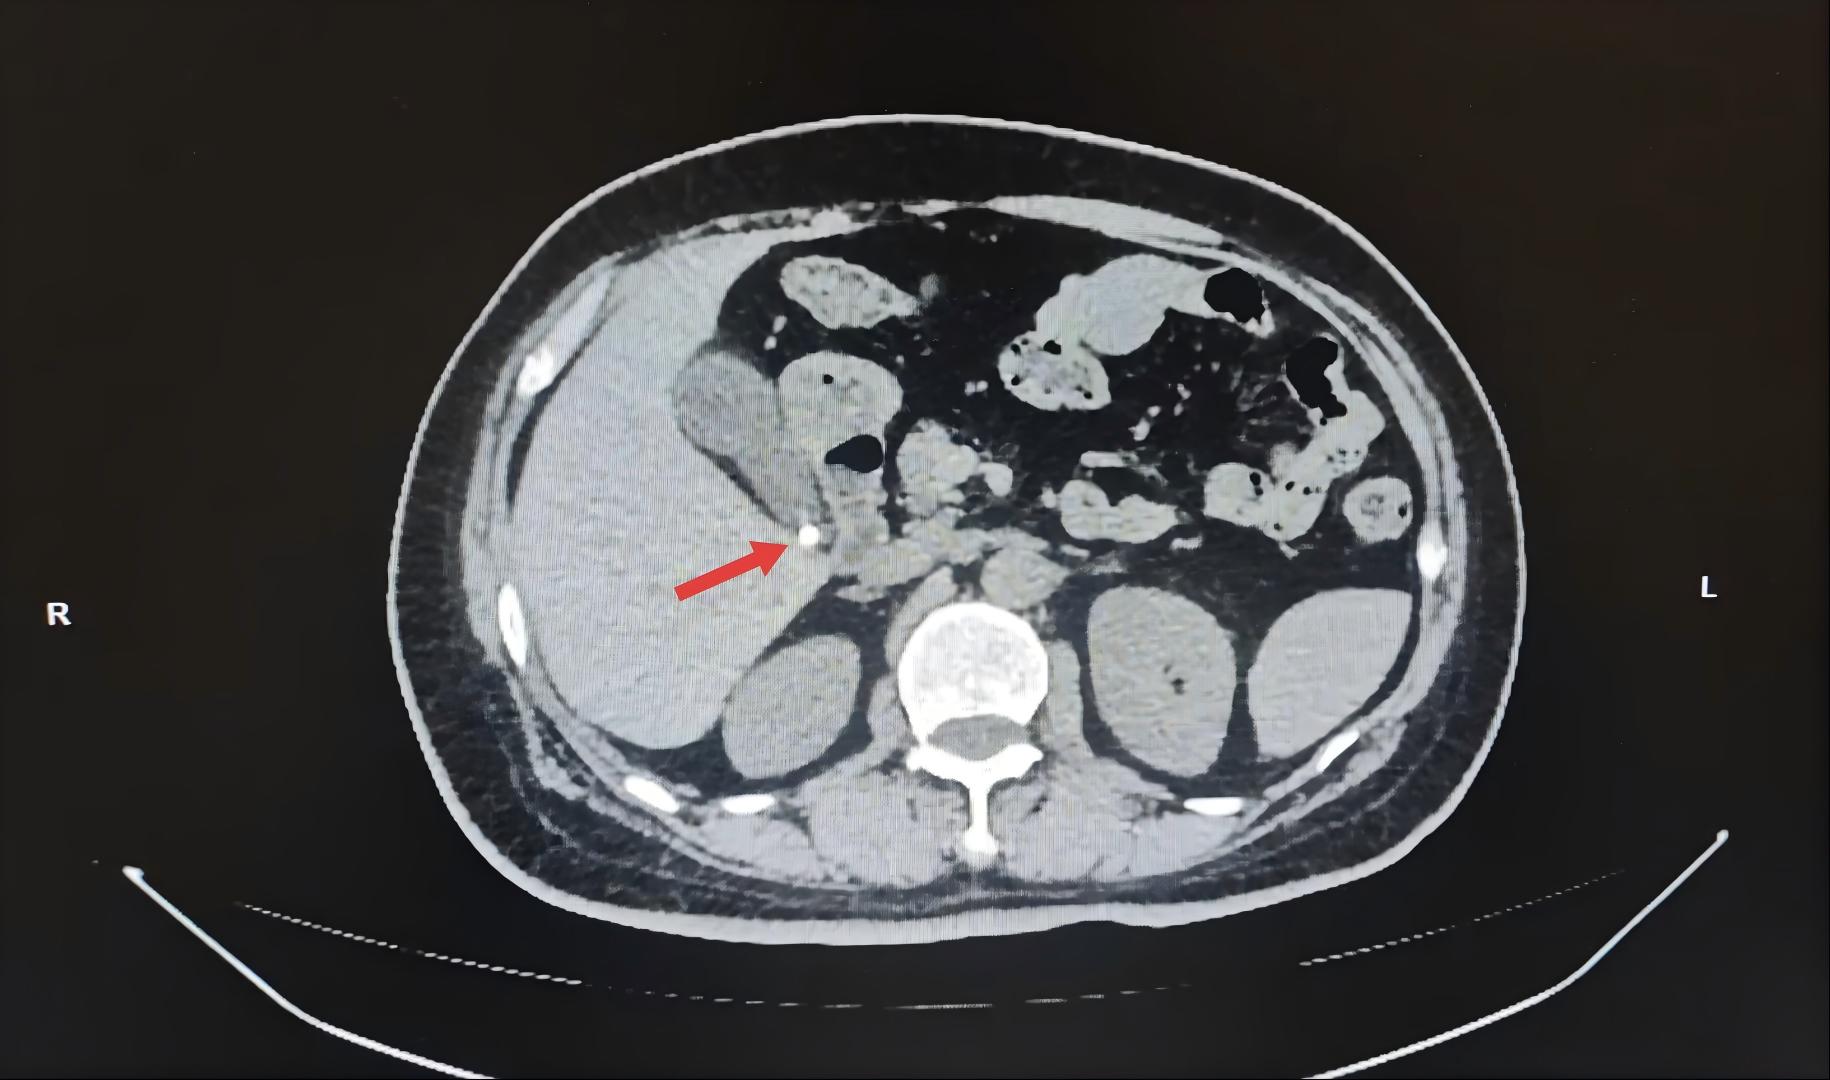

作为我国腹腔镜外科技术的开拓者之一,胡三元教授推广腹腔镜技术已有三十多年,对于复杂胆系结石微创外科治疗,以及保胆取石手术有着相当丰富的经验。在完善房大姨的入院检查后,胡院长仔细看了上腹部CT影像。考虑到患者的炎症并不严重,又是单枚内径约0.4cm的小结石,可以考虑保胆取石术。为了缓解患者及家属的焦虑情绪,胡院长耐心讲解了保胆取石术的治疗过程及保留胆囊的优势。既能保留胆囊,又可以将结石一次取净,达到去除病因、术后恢复快的效果,房大姨和家人很快做出了他们认可的决定。经过积极的术前准备,评估患者耐受手术,由胡院长领衔的普外科、麻醉科及手术室护理人员组成的专家团队在全麻下行腹腔镜-胆道镜联合保胆取石术。腹腔镜所呈现的高清视野下,团队在胆囊底部切开一个小口,置入胆道镜,直视下用取石网篮取出结石,再通过胆道镜反复探查,确认没有残余结石后缝合切口,历经一小时手术结束。